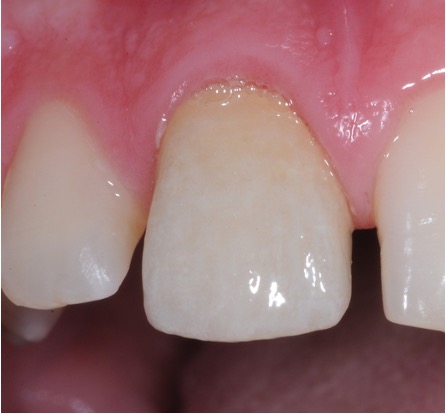

Secondary root canal treatment

Injury to the tooth can cause the root canal to shrink. High magnification and fine ultrasonic instruments are used to locate the root canal.

Fractured teeth

In this case a repeat root filling was completed. This is to minimise risk of infection from the exposed existing root filling. A fibre post and core was placed to build up the tooth sufficiently to retain a crown. This was then restored with an all ceramic crown. If there is insufficient tooth structure sometimes surgery can be carried out. In other cases it may not be possible to restore the tooth.